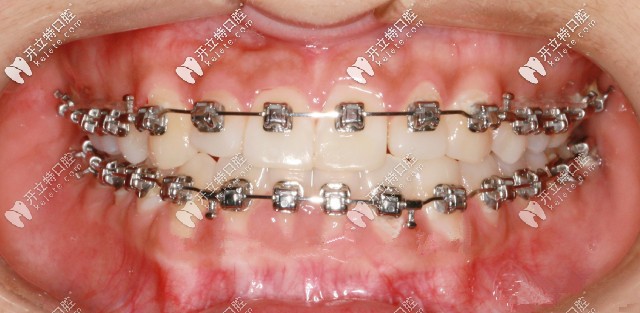

先戴頜墊再做矯正

此案例是戴頜墊3個月左右,解除反頜后開在粘接托槽